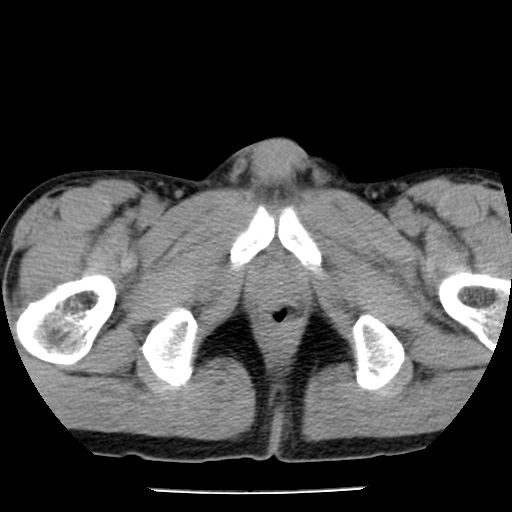

男,59岁,“结核性胸膜炎”30余年,胸部经常疼痛,多次x检查提示“肺部”炎症。腹部疼痛5日,b超提示:“肝内短管结石,余显示不清,建议进一步检查。”

两肺结核并右侧胸腔积液;脾脏、腹腔及腹膜后淋巴结结核[陈旧性];肝内胆管结石

胸部腹部都是结核(双肺。纵隔淋巴结,肝脏,脾脏,肠系膜)

两肺结核并右侧胸腔积液;脾脏、腹腔及腹膜后淋巴结结核[陈旧性];肝内胆管结石。直肠息肉?